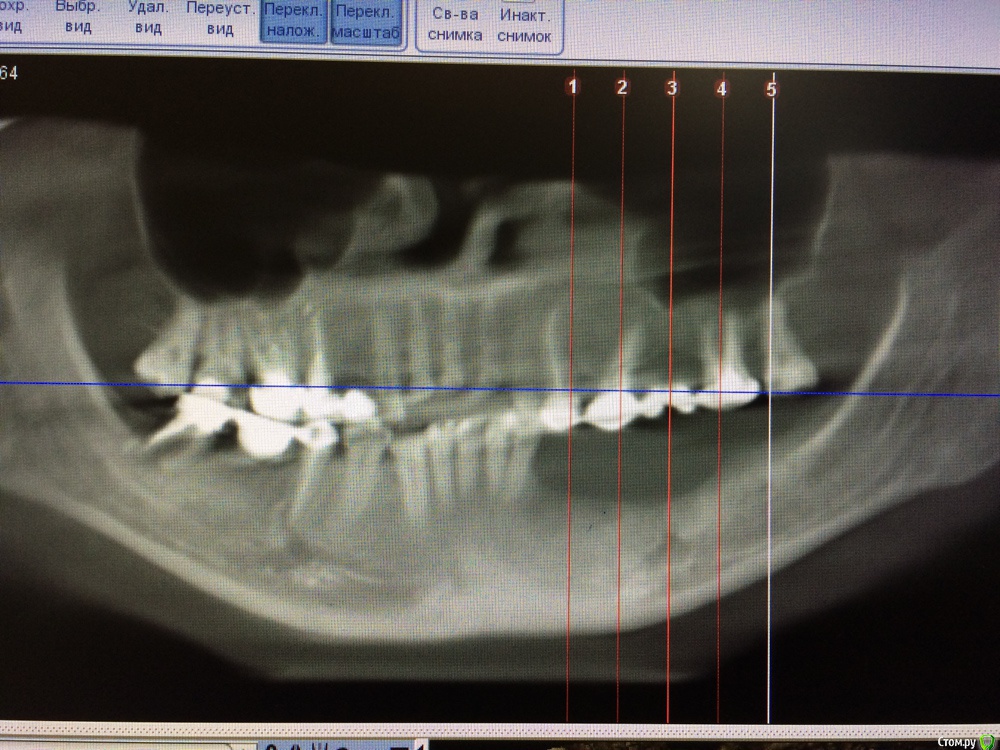

Игнатович Опубликовано 2 марта, 2015 Поделиться Опубликовано 2 марта, 2015 Доброго времени суток. Сам я ортопед. Вашему вниманию представляю пару снимков и хочу спросить совета: что делать с левой стороной нижней челюсти???Планируется замена МК конструкций на верхней челюсти, изготовление ДЦ коронок на инд абатментах на 11,21,22, ламинаты-полукоронки-коронки на фронт верх и низ... Мост на 45-47 нас покинет, так же, как и сам 47. Больше всего волнует низ левая сторона, атрофия значительная, узкий альвеолярный гребень, зубы удалены около года. Для пациентки более предпочтительна несъёмная конструкция.Варианты, которые приходят в голову:-костная пластика и имплантация двухэтапными имплантатами? (где брать костные блоки и мягкие ткани, гарантирован ли результат?? и через сколько после операции можно будет протезироваться?) -имплантация одноэтапными имплантатами и немедленная нагрузка металлопластмассовой шиной (но какова получится эстетика и не вынесет ли она коронки вместе с имплантатами)???-съемник (как вариант бюгельный ацеталовый)???СПАСИБО!) Ссылка на комментарий

Lolopop Опубликовано 2 марта, 2015 Поделиться Опубликовано 2 марта, 2015 Доброго времени суток. Сам я ортопед. Вашему вниманию представляю пару снимков и хочу спросить совета: что делать с левой стороной нижней челюсти???Планируется замена МК конструкций на верхней челюсти, изготовление ДЦ коронок на инд абатментах на 11,21,22, ламинаты-полукоронки-коронки на фронт верх и низ... Мост на 45-47 нас покинет, так же, как и сам 47. Больше всего волнует низ левая сторона, атрофия значительная, узкий альвеолярный гребень, зубы удалены около года. Для пациентки более предпочтительна несъёмная конструкция.Варианты, которые приходят в голову:-костная пластика и имплантация двухэтапными имплантатами? (где брать костные блоки и мягкие ткани, гарантирован ли результат?? и через сколько после операции можно будет протезироваться?) -имплантация одноэтапными имплантатами и немедленная нагрузка металлопластмассовой шиной (но какова получится эстетика и не вынесет ли она коронки вместе с имплантатами)???-съемник (как вариант бюгельный ацеталовый)???СПАСИБО!) кт есть?? очень информативно было бы,дефект не маленький, Ссылка на комментарий